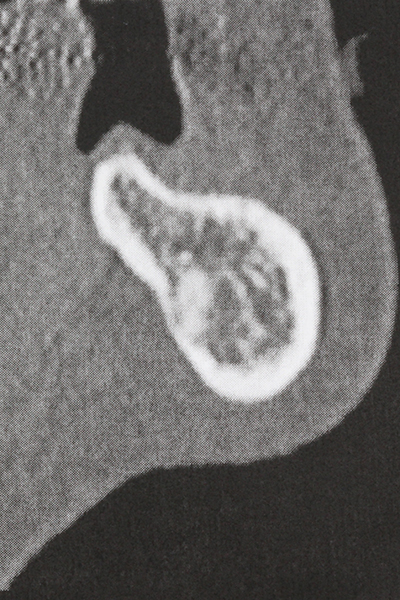

La preparazione della finestra laterale durante un rialzo del pavimento sinusale esterno è complicata, in particolare per gli implantologi con poca esperienza chirurgica. La rimozione della copertura ossea del seno senza danneggiare la membrana schneideriana sottostante è solo una parte dell'operazione: dopo aver stabilito un accesso adeguato, la membrana interna del seno deve essere spostata con cautela per far spazio ai materiali di accrescimento o agli impianti. La piezochirurgia è utile per questa indicazione in due modi: è possibile utilizzare gli strumenti diamantati per l'ablazione selettiva dell'osso e, se la procedura viene eseguita con precisione, la membrana mucosa sottostante rimane intatta. Le frequenze ultrasoniche permettono anche la separazione della membrana mucosa senza complicanze: le frequenze vengono trasmesse nello spazio compreso tra la membrana mucosa e il pavimento sinusale mediante degli speciali raccordi smussati (Cassetta, Ricci et al. 2012, Pereira, Gealh et al. 2014) (Rickert, Vissink et al. 2013). Di conseguenza, non sorprende che le rivisitazioni attuali del rialzo del pavimento sinusale esterno valutino positivamente l'utilizzo dei dispositivi piezoelettrici, delle superfici non lisce degli impianti e dei materiali di riempimento dell'osso (Wallace, Tarnow et al. 2012).